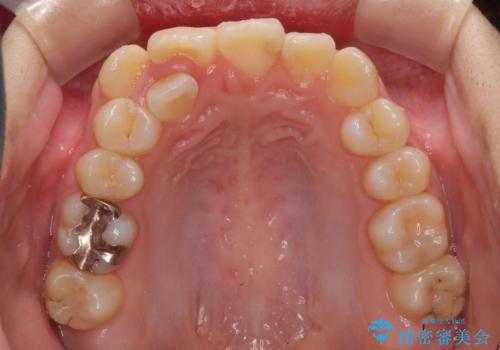

八重歯で正中が右にずれている ワイヤー装置での抜歯矯正で正中位置を改善

- 上下の八重歯と前歯のデコボコを気にして来院された患者様です。

右上の八重歯が特に著しく、上顎正中が右側にシフトしていました。

デコボコが強いため小臼歯4本を抜歯し、上顎正中を左側に移動させるために補助装置を使用して、ワイヤー装置にて矯正治療を行うこととしました。